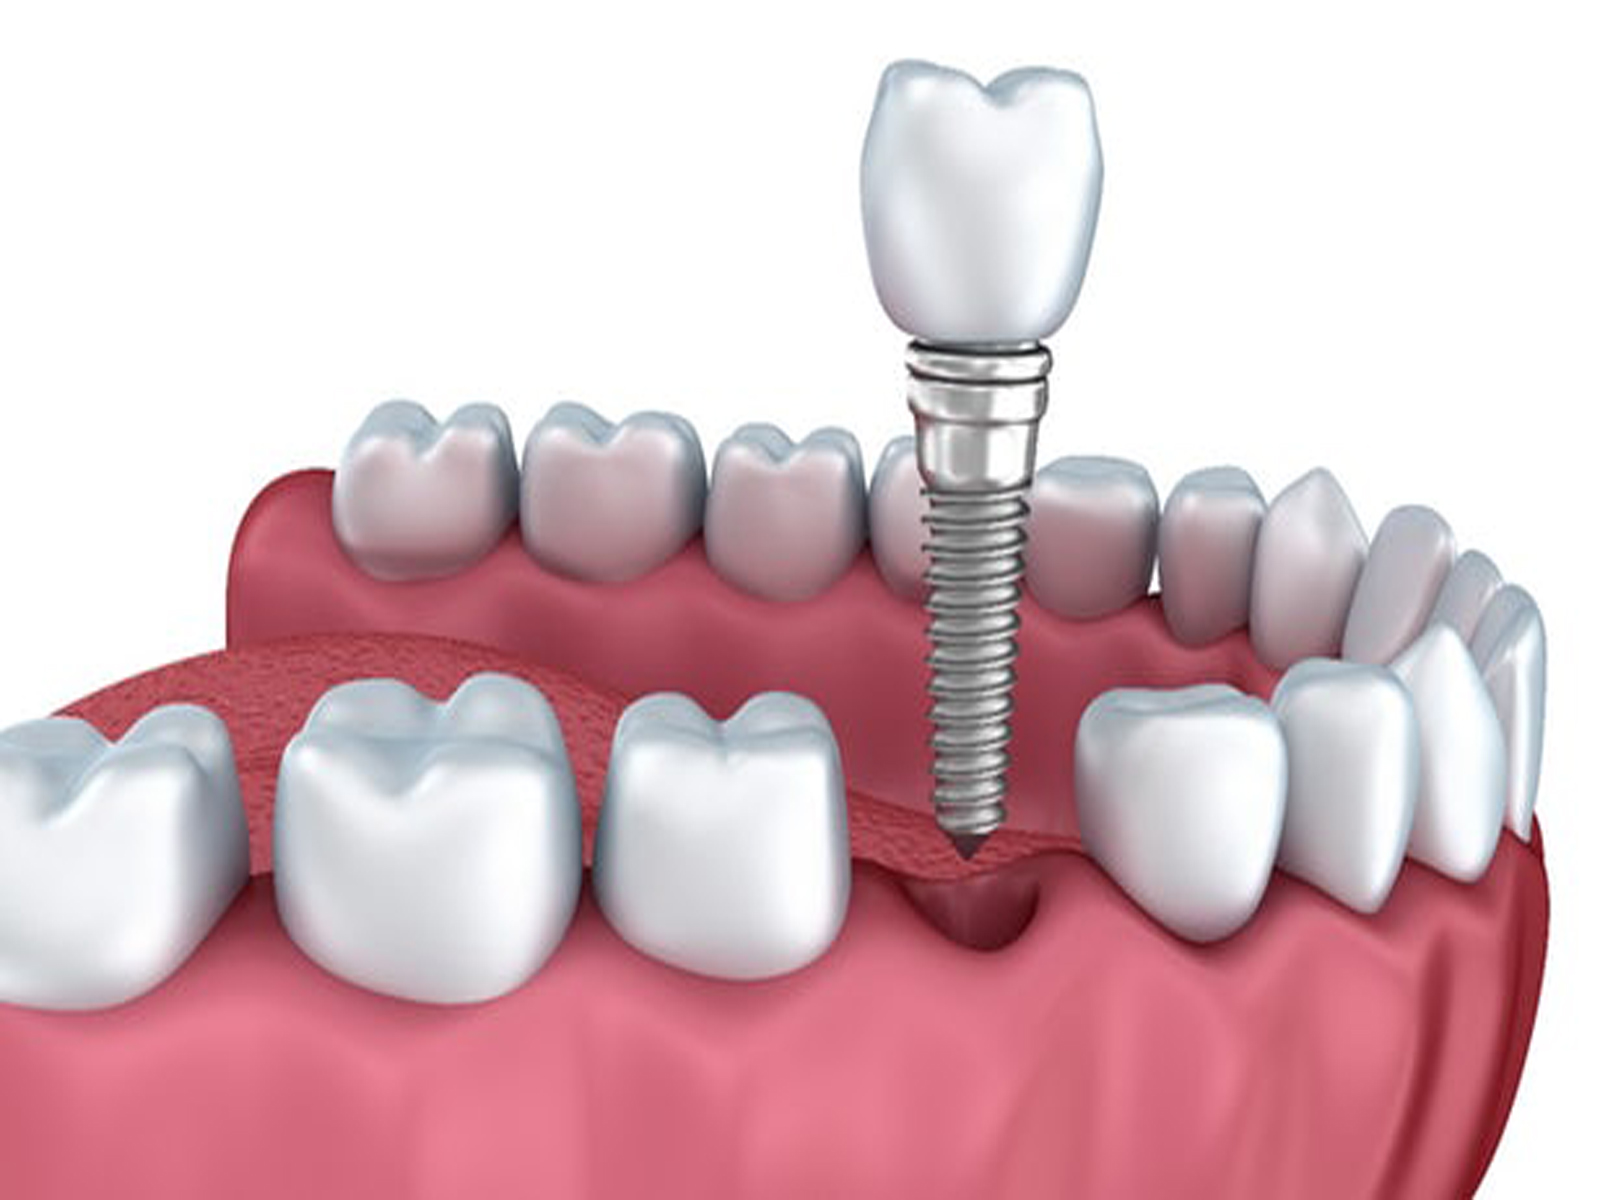

DENTAL IMPLANTS